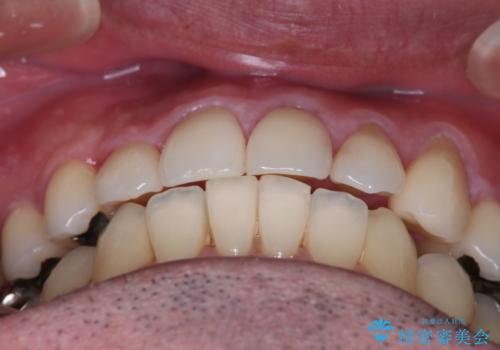

【メタル装置】1本のみ抜歯してワイヤー矯正

- 30代男性

抜歯の本数を最小限に抑えたことで、治療計画も1年5ヶ月と短期間で終了することができ

主訴である前歯のがたつきも改善され綺麗な歯並びになりました。

矯正の装置を除去したタイミングで、ホワイトニングも行うことで歯の色味も白くなりました。